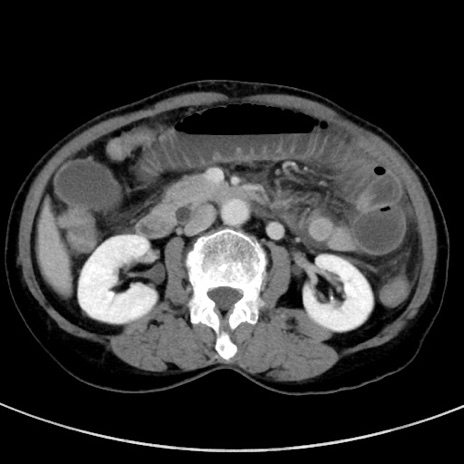

症例23(横断像)

【症例】70歳代女性

【主訴】下腹部痛・嘔吐

【現病歴】2日前より腹痛あり。昨日嘔吐あり。症状改善しないため来院。

【既往歴】胃GISTに対して胃部分切除後。

【身体所見】BT 37.1℃、BP 128/77mmHg、腹部:平坦・軟、下腹部に圧痛あり。

【データ】WBC 10200、CRP 0.31